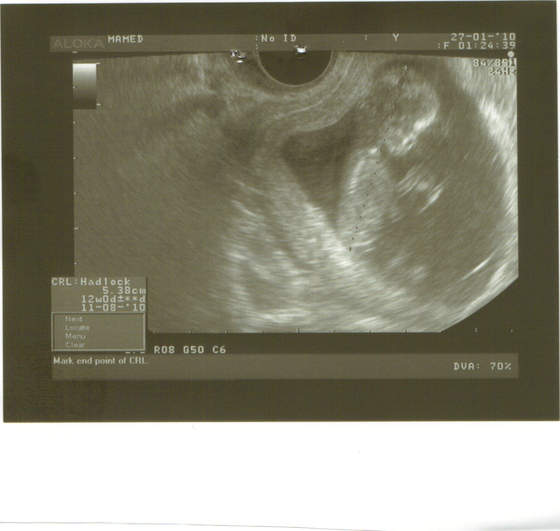

wszystko w jak najlepszym porządku, macha łapkami, kopie nóżkami, a nawet drapie się po głowie. tak sobie myślę, że to już chyba nie fasolka, ale kawał człowieczka

jakie to ważne wiedzieć, że jest OK, normalnie jakbym skrzydeł dostała